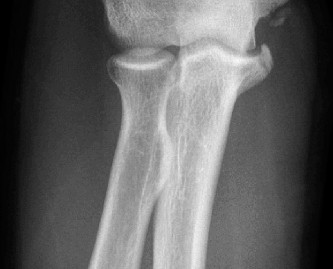

On examination, he has tenderness to palpation over his olecranon and pain with terminal elbow extension. He has no evidence of varus or valgus instability. No pain with resisted wrist flexion. His images are shown (Figs. 2–108 to 2–110).

Figure 2–108

The correct answer is (A). This syndrome occurs most commonly in competitive pitchers, with pain that is worse in the deceleration phase and at terminal extension. The resulting chronic stress results in chondrolysis, osteophyte formation, and attenuation of the MCL. Medial epicondylitis is also common in pitchers, but the pathology is limited to the flexor pronator mass. Pain is over the medial epicondyle and is worse with wrist and forearm flexion. OCD lesions are most common in the capitellum, often present with mechanical symptoms. Olecranon stress fractures result from repetitive abutment into the olecranon fossa. This is a plausible answer, however, the MRI findings are not consistent. MCL rupture is typically acute and is not seen on the MRI shown.

Understand the radiographic findings seen in patients with valgus overload? Identify indications for operative intervention?